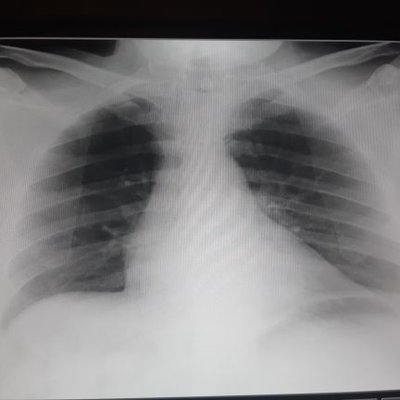

Best Tagalog Pick Up Lines Funny Cheesy Love Sweet kilig 2021. Kadalasan nararanasan lamang ito kapag may butas ang puso ng pasyente. Ayon sa datos sa kada 1000 bagong-silang na sanggol lima sa kanila ay may congenital heart disease.

Maaaring isilang ang isang sanggol ng may sakit sa puso. Ang kondisyong ito ay tinatawag na congenital heart disease CHD. Contextual translation of my butas ang puso into English.

Parang may butas ang puso mo kasi doon ako nabitag at hindi na makakawala Kung may tindahan ako lahat ng tao ibebenta ko ng mura. Panakip-butas hole cover stopgap measure temporary substitute binutasan made a hole in. Habang ang isang binlig ay nasa bahay-bata may butas sa pinaka-dingding ng puso nito.

Himalang nabuhay ang sanggol na may butas sa puso Emma holding her newborn daughter Ramaya. Close your manual and write these six words or phrases in. Maaari ring hindi magkaroon ang pasyente ng pamamanas kung ang mga kidney o bato nito ay walang problema o sira.

Kung magkakaroon ako ng sariling planeta gusto ko ikaw ang axis nito para sayo lang iikot ang mundo ko. Sa sakit na ito ang sanggol ay ipinanganak na may butas ang kanyang puso o kaya naman ay ang mga ugat nito. Sweet Pick Up Lines in Tagalog For Your Crush.